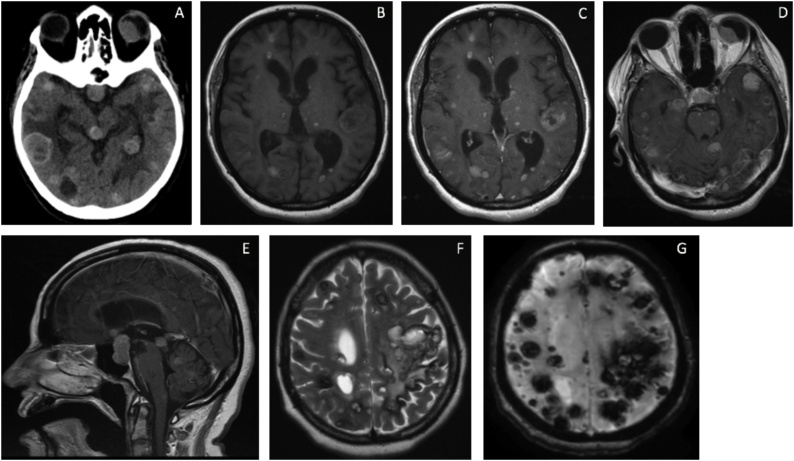

Brain CT followed by MRI (Fig. 1) showed multiple intra-axial supratentorial and infratentorial lesions. The lesions were of variable sizes with the small lesions showing a miliary pattern. Extra-axial lesions involved the sellar-suprasellar region and the left eye. The lesions were hemorrhagic, appearing as blooming artifacts on gradient echo MRI sequence, and resembling metastatic melanoma, metastatic choriocarcinoma, familial cavernous malformations, or amyloid angiopathy. Fluorodeoxyglucose-positron emission tomography CT showed bilateral lung, bilateral mediastinal lymph nodes, liver, and adrenal glands metastases. Craniotomy and biopsy of 3 brain lesions were done.

Fig. 1.

CT axial scan of the brain showing multiple mixed hyper- and hypodensity mass lesions within the supratentorial and infratentorial compartments, in addition to the left eye globe (Fig. 1A). Axial MRI T1 with gadolinium contrast reveals multiple enhancing lesions of supra- and infratentorial compartments, and the left eye globe (Fig. 1B–D). Sagittal MRI T1 with gadolinium demonstrates multiple midline lesions and a large sellar/suprasellar lesion (Fig. 1E). Axial T2 MRI of the supratentorial compartment shows multiple hyperintense lesions with a hypointense rim (Fig. 1F). GRE view of the supratentorial compartment demonstrates many blooming artifacts representing intra-tumoral hemorrhages (Fig. 1G).